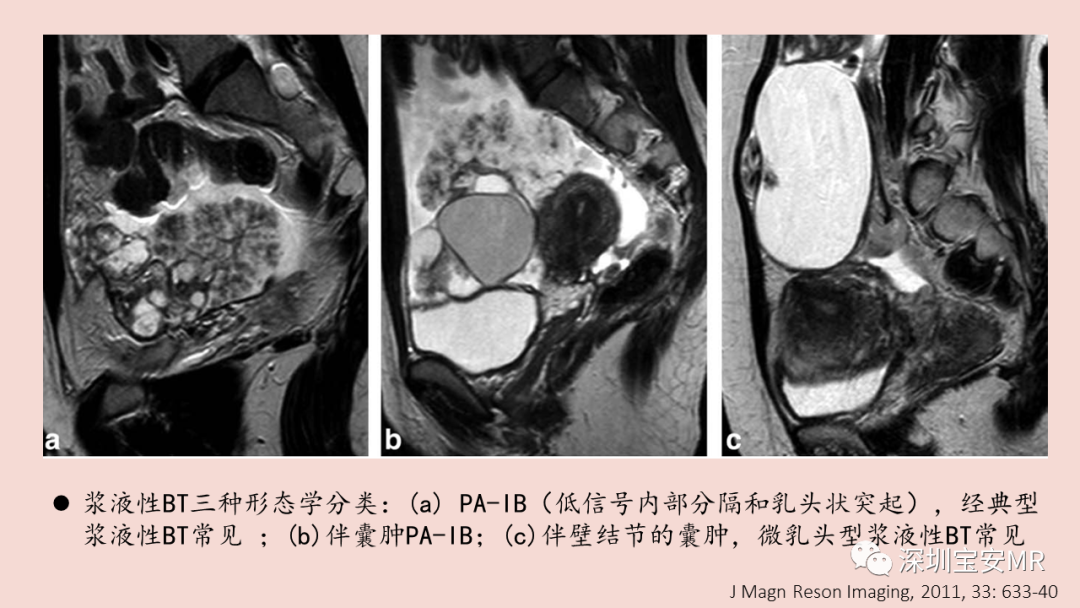

图片